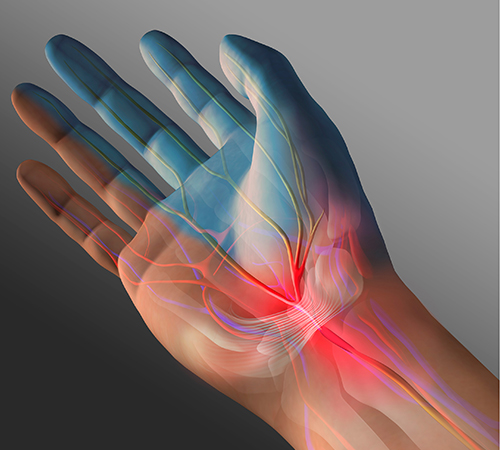

수근관증후군

• 정상

• 수근관증후군

양측성이지만 대부분 많이 사용하는 손에 통증이 나타납니다.

비수술적 치료로도 호전될 수 있으나, 장기간 방치할 경우 수술적 치료를 고려해야 하므로 조기치료가 중요합니다.

• 수근관증후군 진단

1. 신경 타진 검사

정중 신경이 지나가는 손목의 신경을 손가락으로 눌렀을 때,

정중 신경의 지배 영역에 이상 감각이나 통증이 유발되는지 검사합니다.

2. 수근 굴곡 검사

손바닥을 안쪽으로 향하여 손목을 약 1분 동안 심하게 꺾었을 때,

정중 신경의 지배 영역에 통증과 이상 감각이 나타나거나 심해지는지 검사합니다

3. 전기적 검사

무지구 근육(엄지손가락 밑부분의 불룩한 부분)에서 근전도의 이상이 있는지,

손목에서 신경 전달 속도의 지연이 있는지를 검사합니다.

수근관증후군 치료방법

• 비수술적 치료

적절한 휴식과 약물치료, 주사치료, 재활운동 등의 비수술적 치료로 손상부위의 혈액순환을 개선합니다. 증상 초기에는 비수술적 치료만으로도 호전 가능하나, 통증이 지속된다면 수술적 치료를 시행합니다.

• 수술적 치료

‘수근관증후군’의 가장 효과적인 치료는 수근관을 넓혀주는 것입니다. 수근관 유리술(Carpal tunnel release)은 상완신경총마취 후 손목을 2~3cm 정도 절개한 뒤 두꺼워진 인대를 절단하여 정중신경이 눌리는 것을 풀어주는 수술법입니다. 수술 시간은 5분 이내로 매우 짧고 증상도 금방 호전되지만, 4주간은 주의해야 합니다.